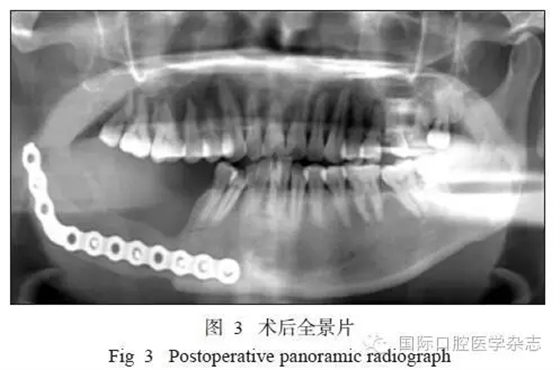

1.5 隨訪

患者術(shù)后切口愈合良好,牙無松動(dòng),咬合關(guān)系良好。術(shù)后復(fù)查顯示傷口愈合良好,骨斷端生長良好(圖3)。